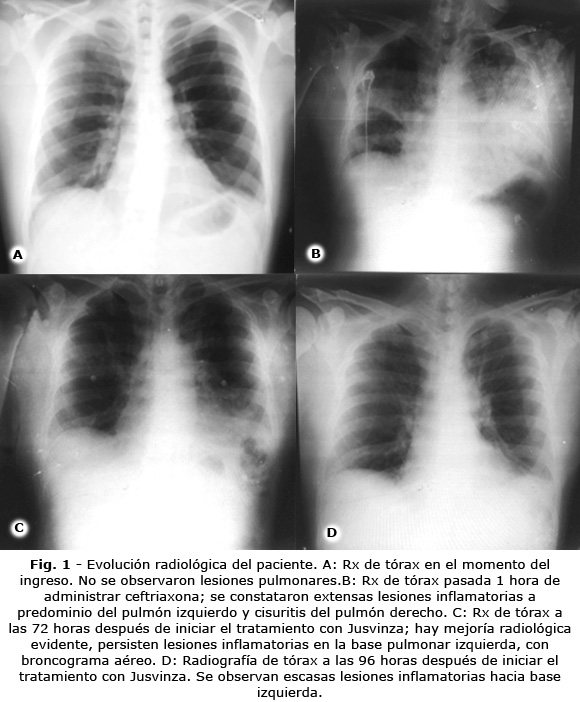

En el momento de ingresar presentó fiebre de 38 °C e hipotensión arterial (80/40 mmHg). No se auscultaron soplos, ni estertores. No se observó ingurgitación yugular. Presentó una frecuencia cardíaca de 110 por minuto y respiratoria de 25 por minuto. En la radiografía de tórax no se percibieron lesiones pulmonares (Fig. 1A). Tampoco presentó alteración del estado neurológico. En la exploración del abdomen se evidenció hepatomegalia de 2 cm, con bordes romos y no dolorosa.

La radiografía de tórax mostró extensas lesiones inflamatorias a predominio del pulmón izquierdo y cisuritis del pulmón derecho (Fig. 1B). A partir de estos elementos, se decidió recurrir a la intubación orotraqueal.

A partir de entonces el paciente se mantuvo con oxígeno suplementario por máscara facial y en decúbito prono intermitente, durante otras 48 horas. Continuó evolucionando favorablemente (Fig. 1C, Fig. 2D, tabla 2), el INL disminuyó a 4 y los parámetros metabólicos tuvieron tendencia a la normalización (tabla 1), lo cual posibilitó su egreso. El paciente fue seguido en consulta externa hasta su completa recuperación.